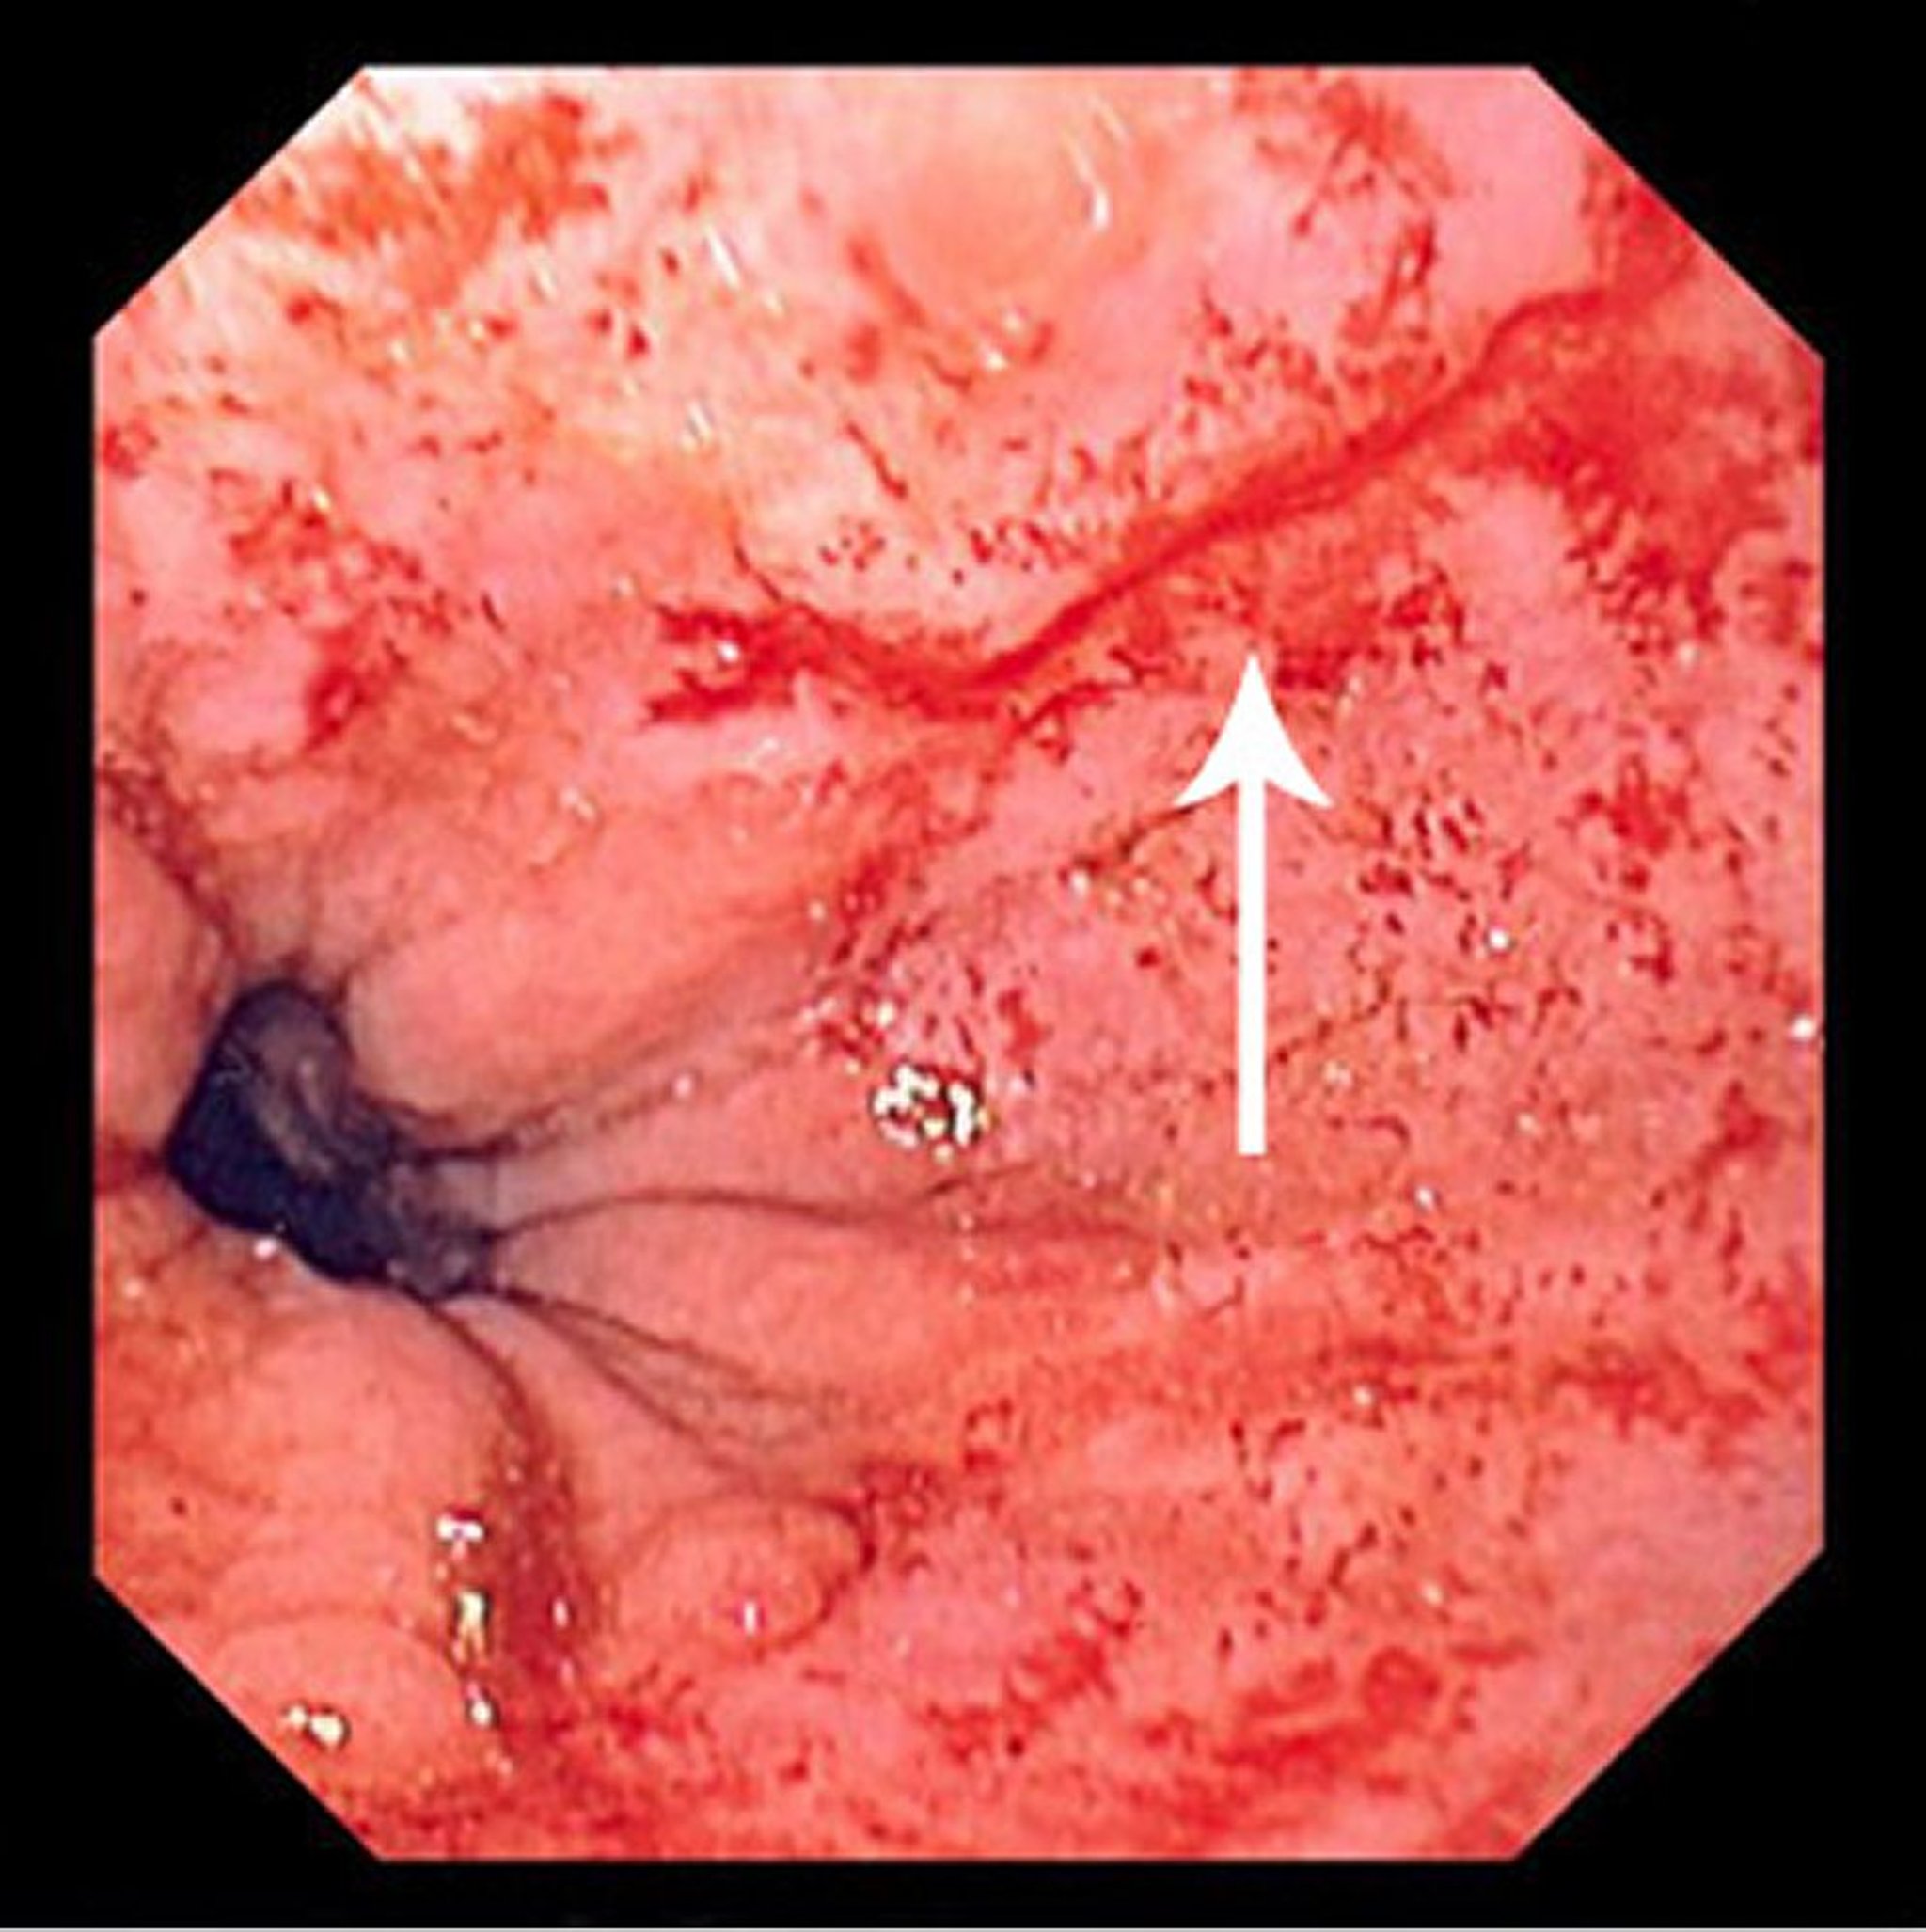

マロリー-ワイス症候群の裂傷

この画像には,扁平円柱上皮接合部の直上から始まり口側に伸びる細い線状の裂傷(矢印)が写っている。

Image provided by David M.Martin, MD.